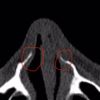

ich hatte vor vier Jahren eine Nasen op und seit dem extreme Probleme beim Atmen. Nun wurde bei der ct Auswertung beim HBO festgestellt,...